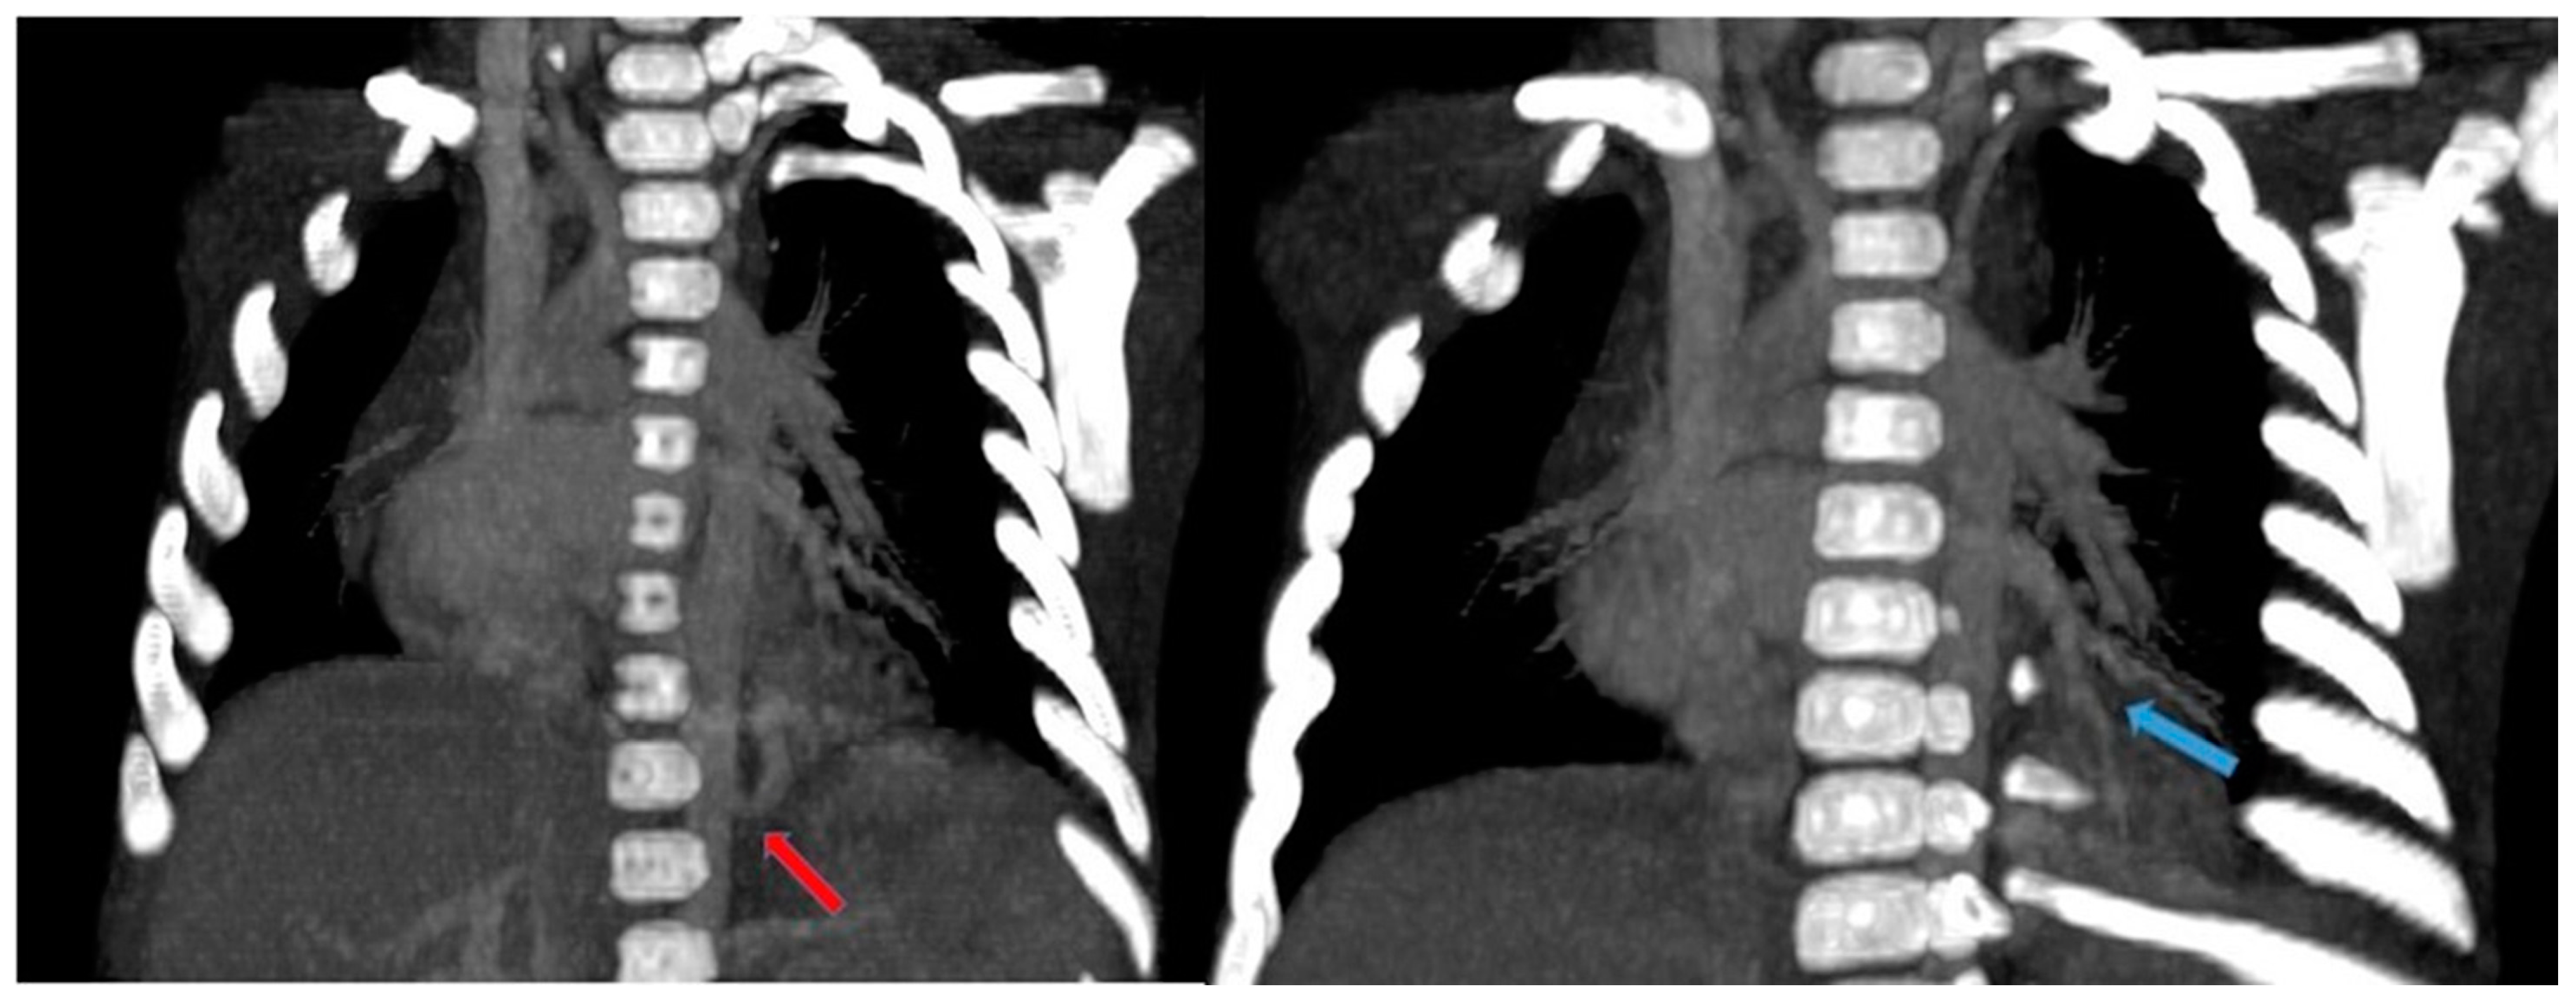

3.6.1. Pulmonary Sequestration